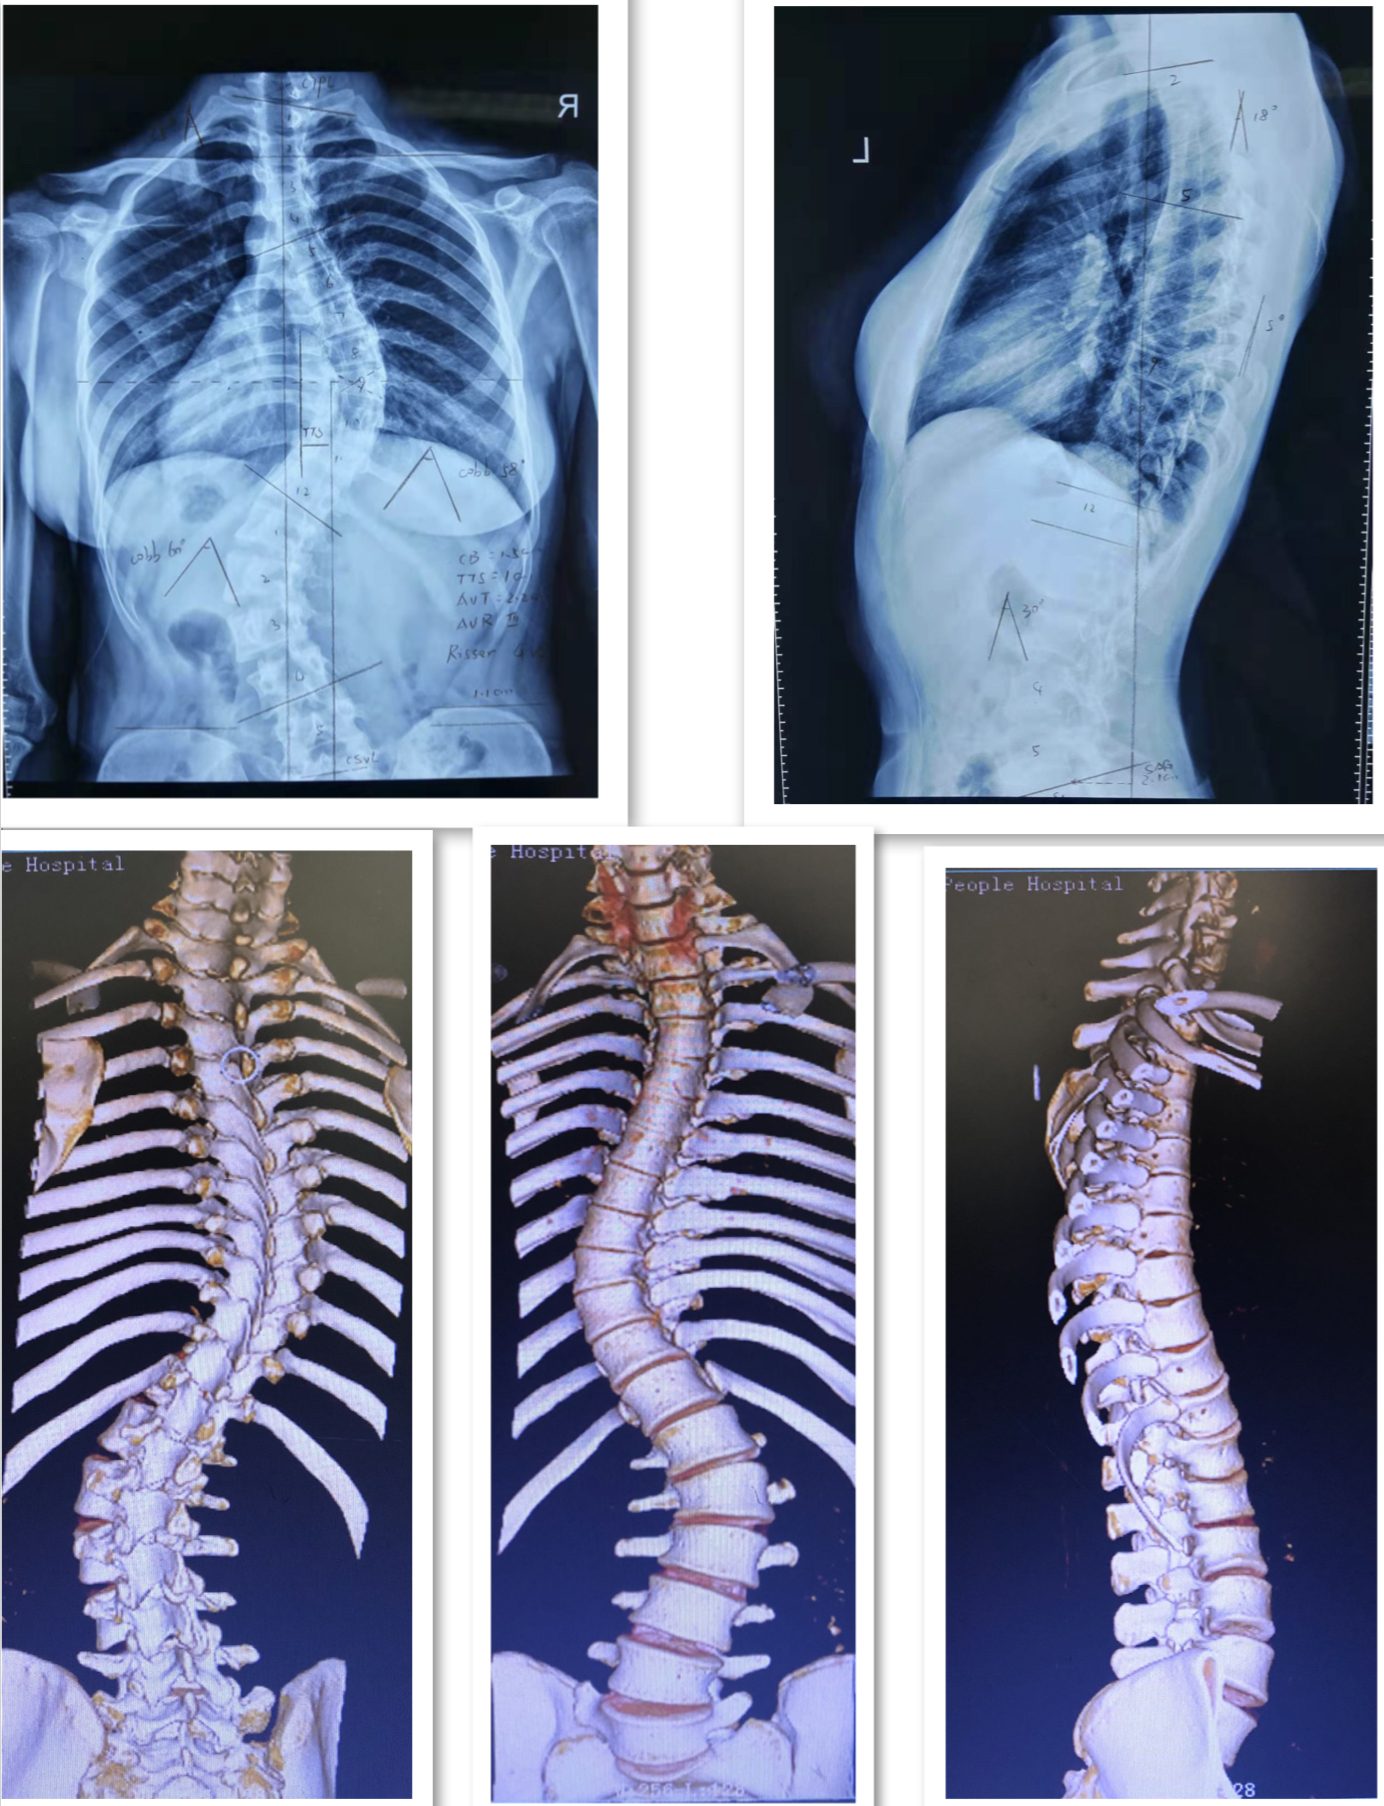

病例三:患者陈某,女性,19岁,云南省昭阳区人,因“发现胸腰背部畸形3年余”入院,诊断为:脊柱侧凸畸形并功能障碍。行经后路胸椎SPO截骨矫形钉棒系统内固定融合术。

术前DR及CT

术后DR

术前术后站立位对比